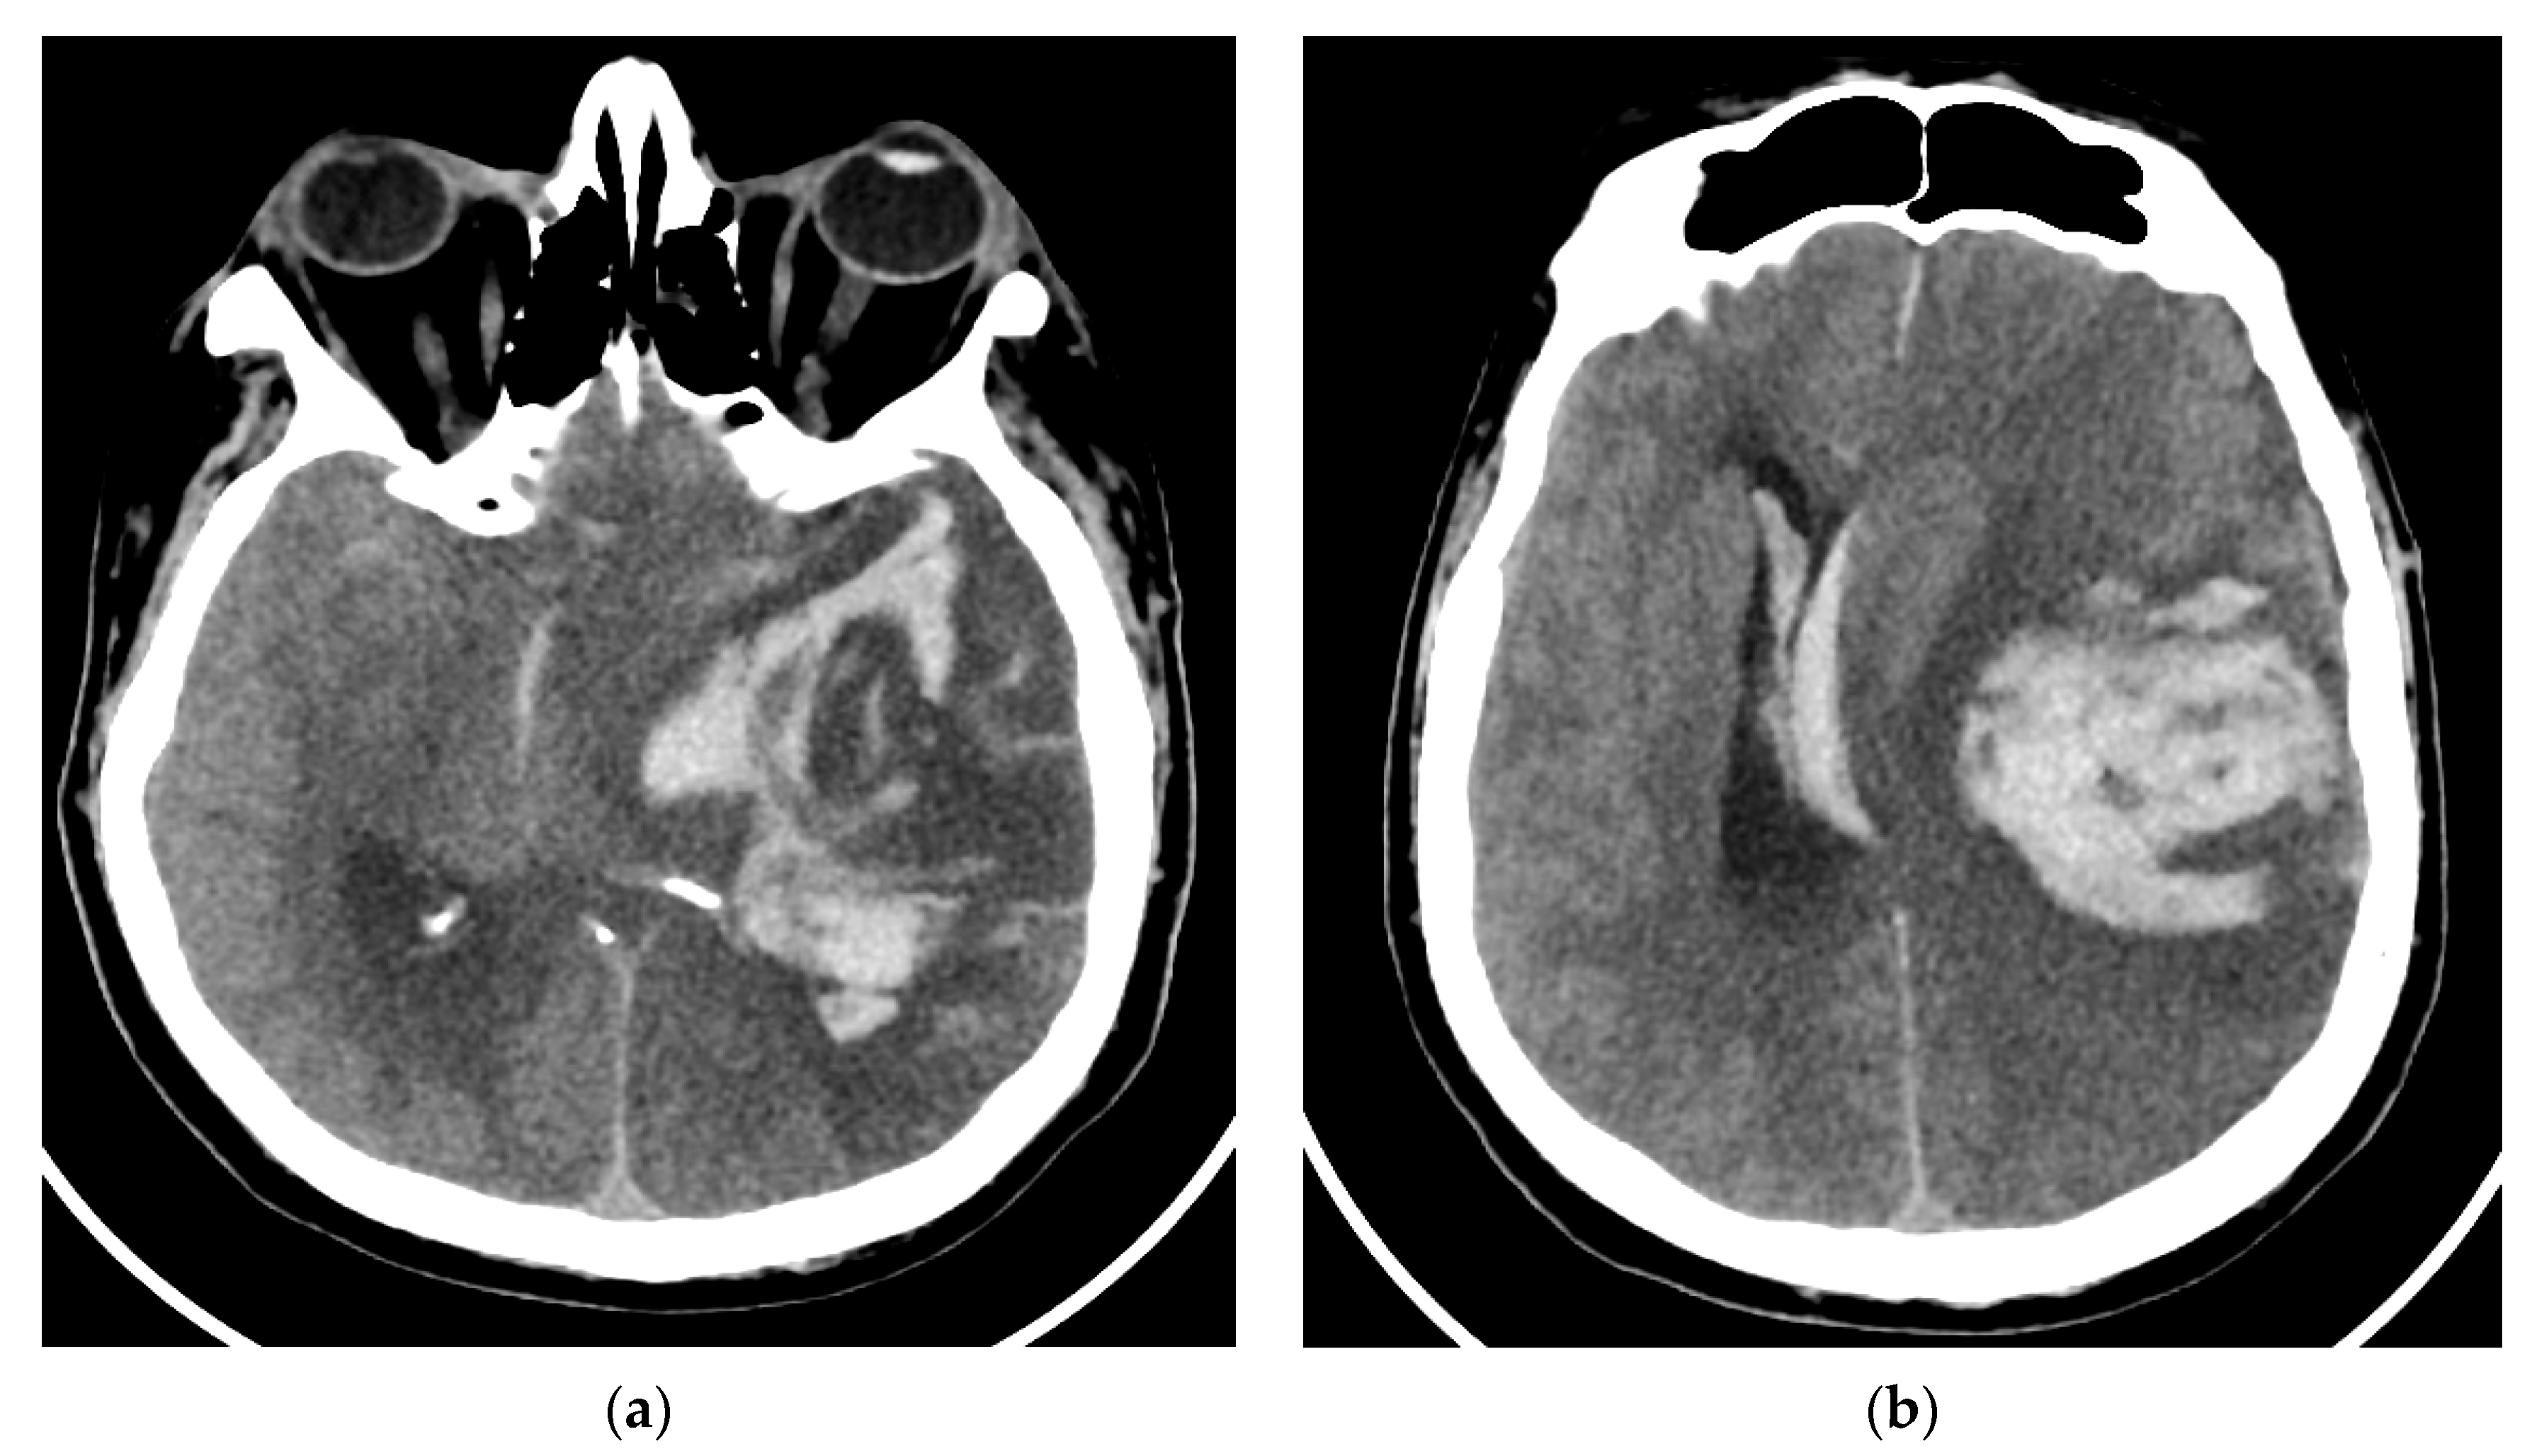

Contrast-enhanced head-computed tomography (head-CT) was conducted upon hospital admission and demonstrated hyperattenuation of the left cavernous sinus and left lateral sinus, which was concerning for sinus thrombosis. MRI of the brain and orbits with and without contrast, in addition to magnetic resonance angiography (MRA)/magnetic resonance venography (MRV) of the head, showed an inflammatory process in the areas of the left cavernous sinus and orbital apex with perineural enhancement surrounding the left optic nerve sheaths. The presence of thrombus in the cavernous sinus was refuted by cerebral MRA/MRV. No vascular malformation of the left internal carotid artery was found. The MRI findings were suggestive of Tolosa–Hunt syndrome (Figure 1).

Figure 1.

MRI T2 axial Flair (a) and coronal T1 FSE (b) images demonstrated perineural tissue extending into the left cavernous sinus. Postcontrast T1 axial FSE (c) and coronal T1 FSE (d) images showed an inflammatory process involving the left cavernous sinus and orbital apex with perineural enhancement surrounding the left optic nerve sheath. MRI: magnetic resonance imaging; Flair: fluid attenuated inversion recovery; FSE: fast spin-echo.